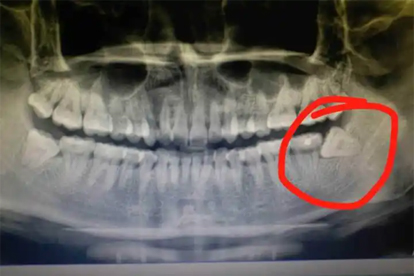

拔完智齿后可以遵医嘱使用阿莫西林胶囊、甲硝唑片、头孢呋辛酯片、布洛芬缓释胶囊、对乙酰氨基酚片等消炎药。智齿拔除后可能出现局部肿胀、疼痛或感染,建议及时就医,在医生指导下合理用药。